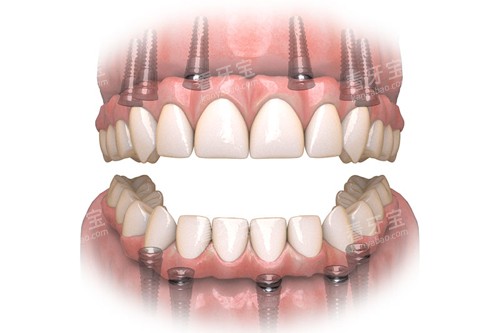

全口吸附性义齿是一种采用特殊设计的修复体,通过功能性印模技术和边缘封闭系统,在口腔内形成稳定的负压吸附力,使假牙能够紧密贴合牙槽骨黏膜表面。与传统活动假牙相比,它的稳固性和舒适度都有显著提升,外观也更接近自然牙齿。